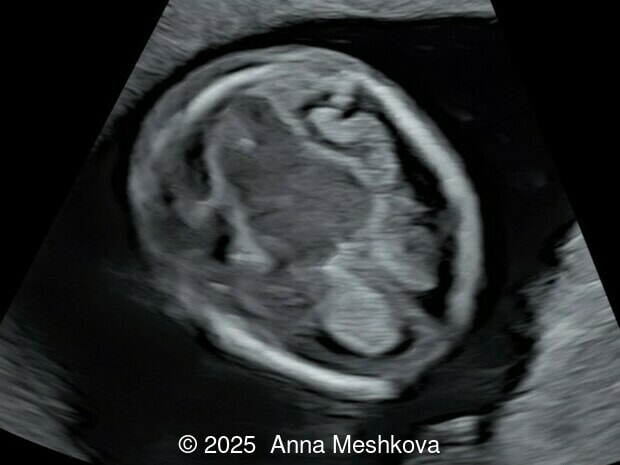

• Image 1:  Transverse section of the brain at the level of choroids. Subtle supporting sign of relatively large choroid plexuses and low surrounding cerebrospinal fluid known as the "dry brain" sign.

4.  Dry Brain Sign is characterized by an exaggerated size of the choroid plexuses filling the lateral ventricles due to diminished cerebrospinal fluid in the ventricular system.  Unidirectional leakage of fluid towards the open spinal defect results from a pressure gradient between the “high-pressure” CSF-filled choroid ventricles and, “low-pressure” spinal cord, which produces posterior and caudal displacement of the mesencephalon. As a result, the reduced fluid in the lateral ventricles causes the choroid plexuses to fill the cranial cavity [4-5].

Dry brain sign is demonstrated in the axial view of the fetal head at 13 weeks gestation. Note the large and long choroid plexus in comparison to head size in a fetus with open spina bifida.

Image 10 Dry brain sign is demonstrated in the axial view of the fetal head at 13 weeks gestation. Note the large and long choroid plexus in comparison to head size in a fetus with open spina bifida.